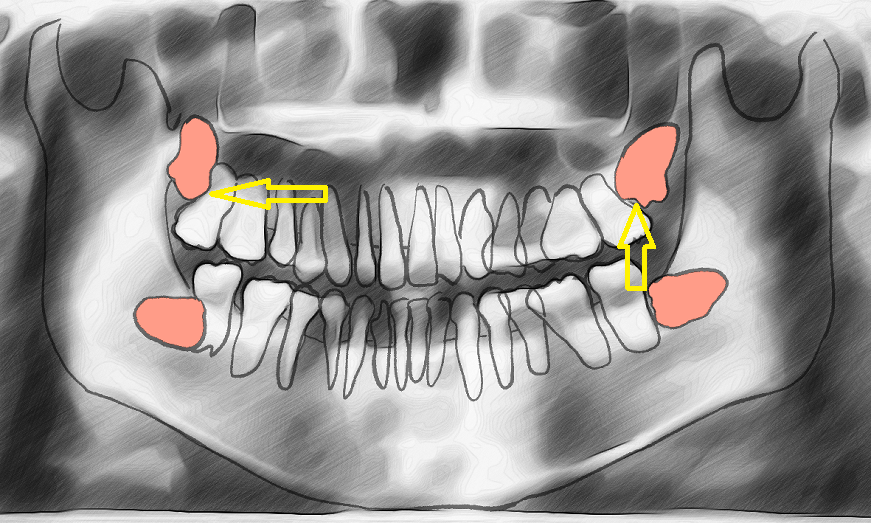

어금니 조지고 있는건 빼는게 좋아보여

오른쪽 위에서 사이에 썩는거만조심하면 될듯

신경이랑 얽혀있으면 못빼는게 맞지...... 근데 저건 잇몸 생각해봐도 최소 좌상악은 노출되어있고 우상악은 어금니 밀어내서 뿌리 휘어져있는데 늙고병든 다음에 ㅈ되기싫음 빨리 빼면서 교정 시작하는게 맞다봄 | 25.12.04 20:29 | | |

버티컬이어도 뽑는 게 맞는건데 아예 호라이젠털인데 이걸 두자 했다고? 남은 어금니 다 썩어 문드러지게 하고 싶지 않음 다 빼라 상악도 제대로 올라오더라도 인접면충치 각이네

작성자가 그린 그림이 실제 엑스레이를 반영한다면 실제 잇몸라인은 여기서 붉은색 라인에 가까움 그러면 4개 사랑니가 모두 잇몸 안쪽에서 완전매복상태라 성인 기준으로 더 이상 성장가능성이 없다면 안뽑아도 됨 일부가 잇몸 밖으로 드러나는 경우에 맞닿은 이가 썪는거고, 밀린다는 얘기도 성장기에나 적용되는거라 작성자가 완전성인인 경우엔 특별한 사정이 없다면 뽑지 말라고 할걸 | 25.12.04 20:28 | | |